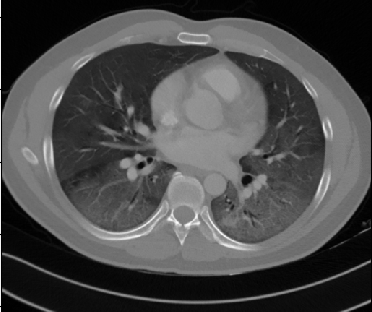

Figure 1 shows four CT scan slices, two from a non-COVID-19 CT scan, on the left and two from a COVID-19 scan, on the right. Bilateral ground glass regions are seen especially in lower lung lobes in the COVID-19 slices.